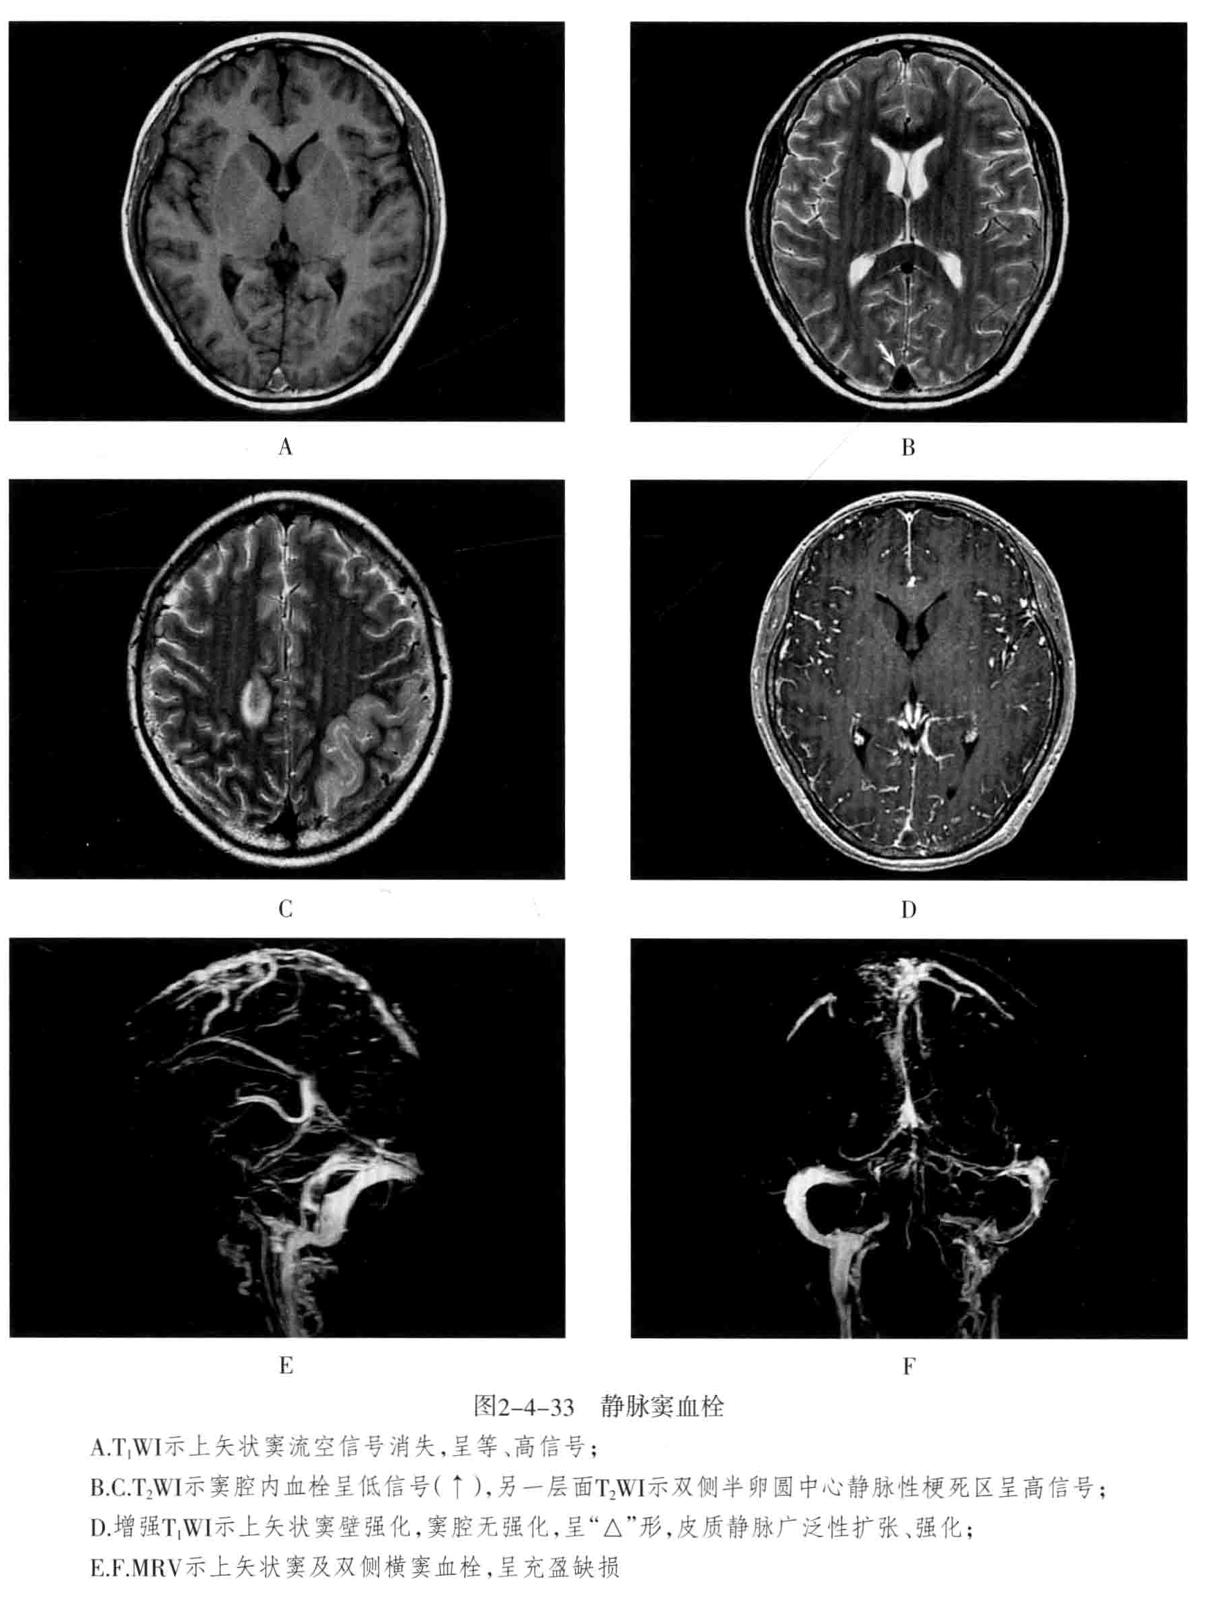

五、静脉及静脉窦闭塞

多由血栓形成所致,常继发于面部或全身感染、严重脱水,脑外伤、产褥期、脑肿瘤侵犯及血液病等。常引起脑静脉回流障碍,所属引流区发生脑水肿、脑梗死、脑出血。

CT表现:平扫可见闭塞的静脉窦和或脑静脉呈条状高密度,称为“带征”的特征性表现。相应区域可见低密度水肿和脑梗死。增强后静脉窦或脑静脉充盈缺损,血栓不强化,可见“空三角征”。CTA可直接显示静脉窦和脑静脉闭塞的位置和范围及侧支循环通路。MRI上静脉窦流空效应消失。